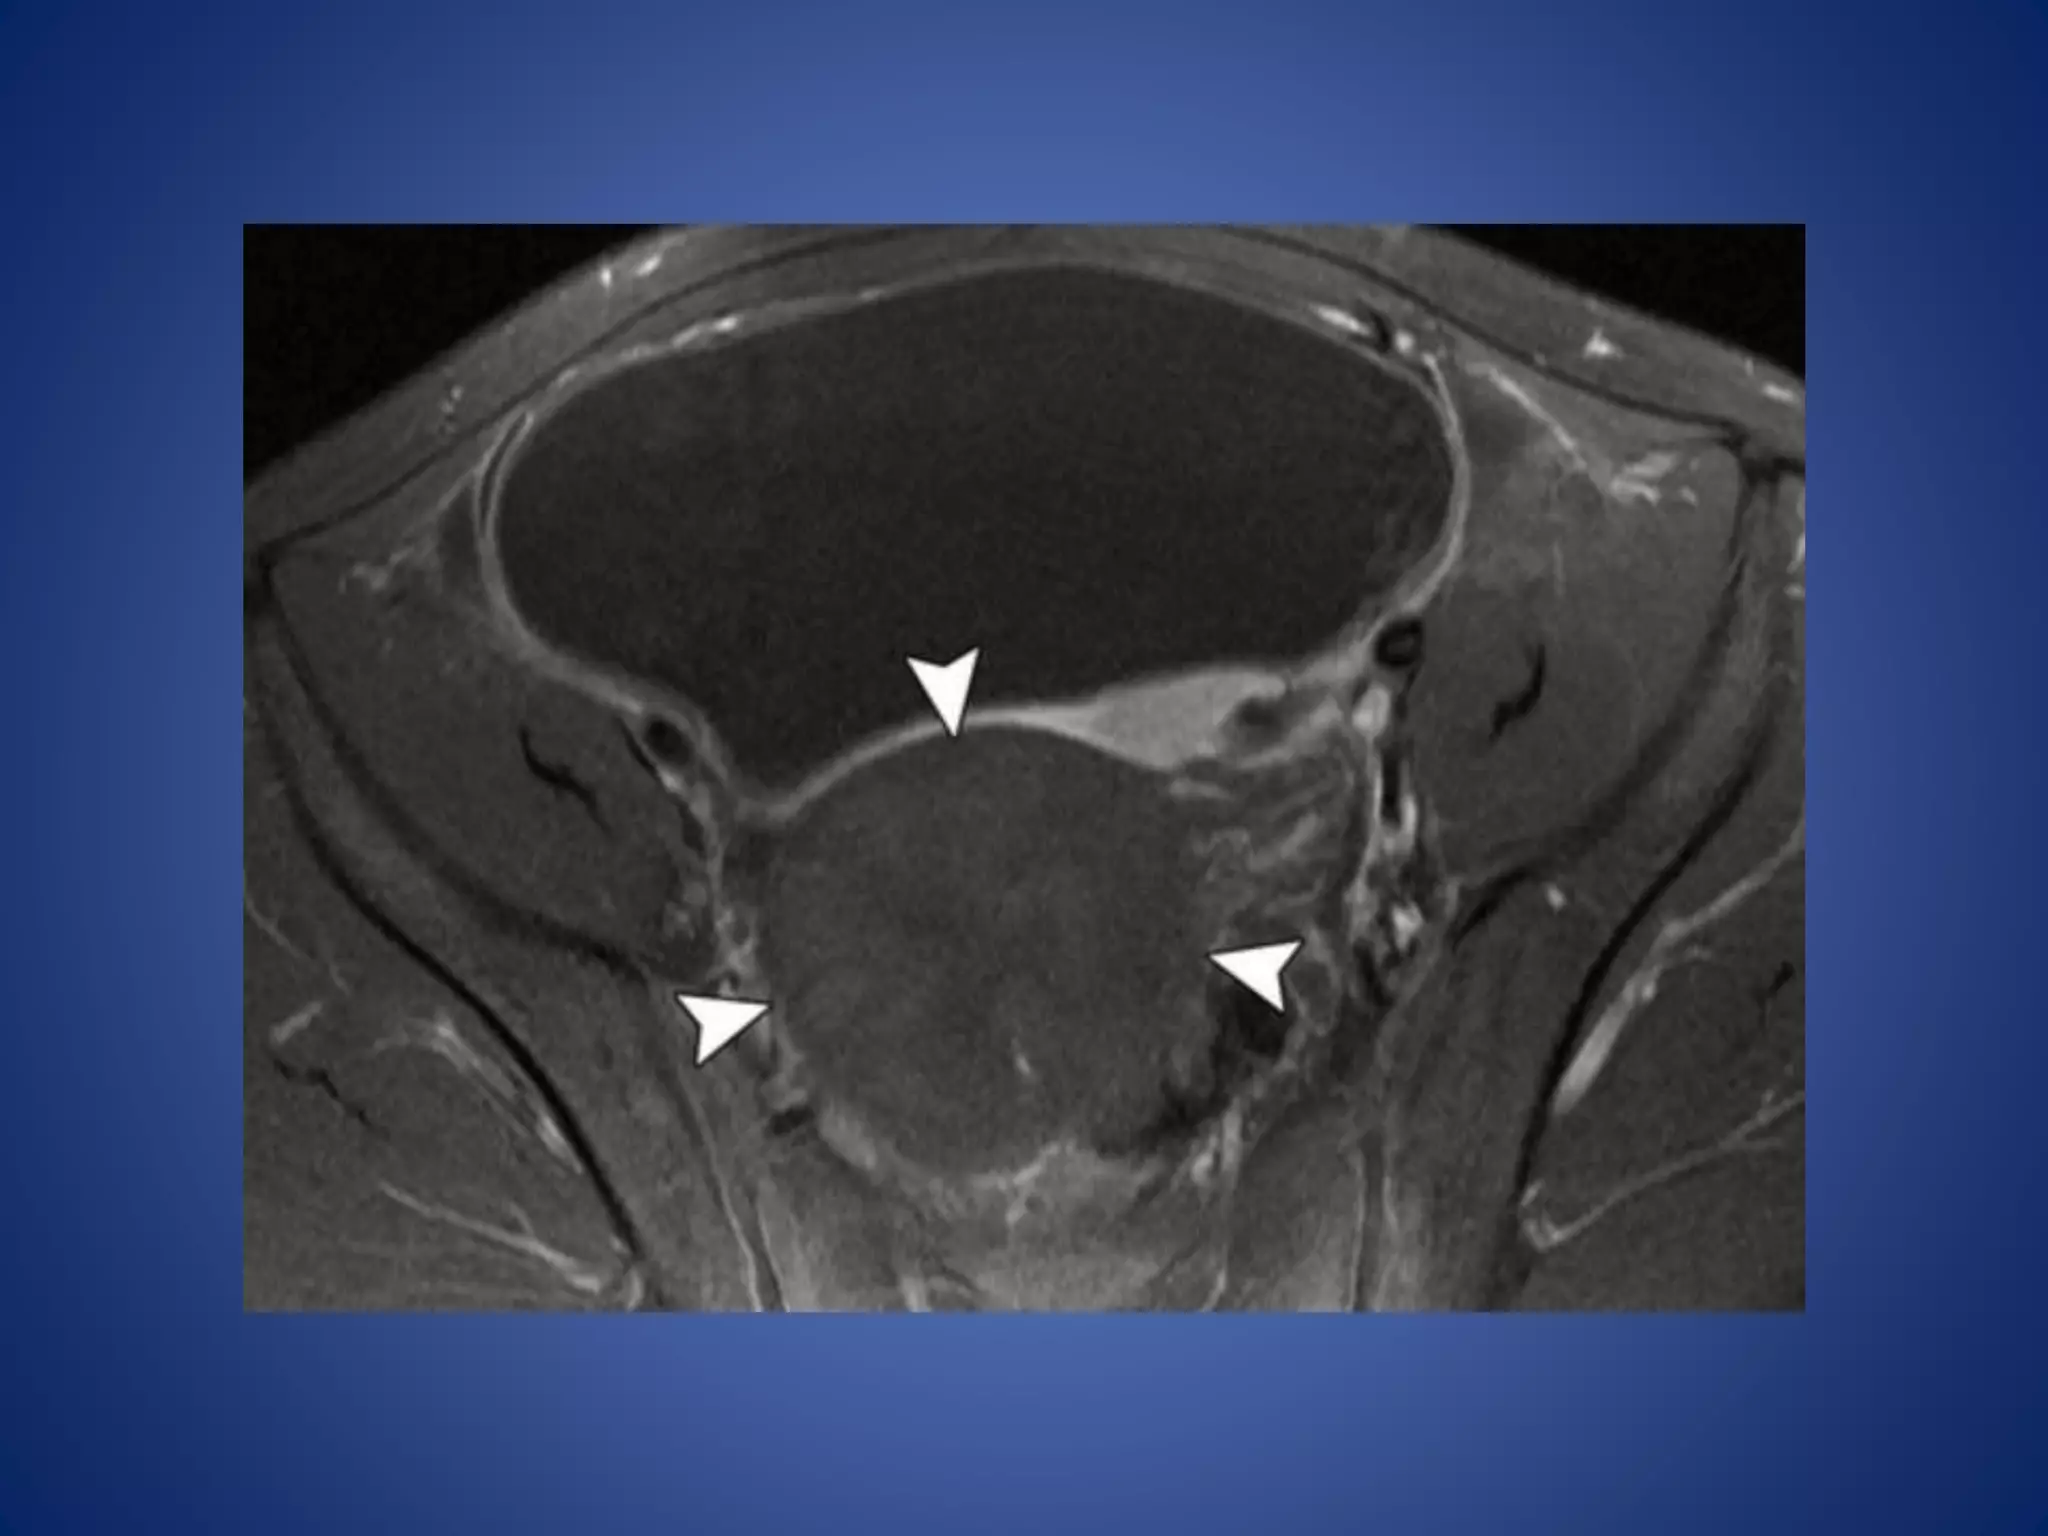

Juvenile GCT ofthe Ovary Juvenile GCT is a malignant primary ovarian neoplasm of children and young adults that is most often characterized by clinical manifestations of steroid hormone overproduction. The lesion is classified as a sex cord–stromal tumor. Imaging Features.— As an ovarian tumor, juvenile GCT is usually initially identified at US, with demonstration of a large mixed cystic and solid mass.

• 61.

US also showsuterine enlargement and pubertal morphology due to estrogen effect

• 63.

At MR imaging,the solid portion of the tumor demonstrates intermediate signal intensity with multiple hyperintense cystic spaces on T2-weighted images, creating a spongelike appearance